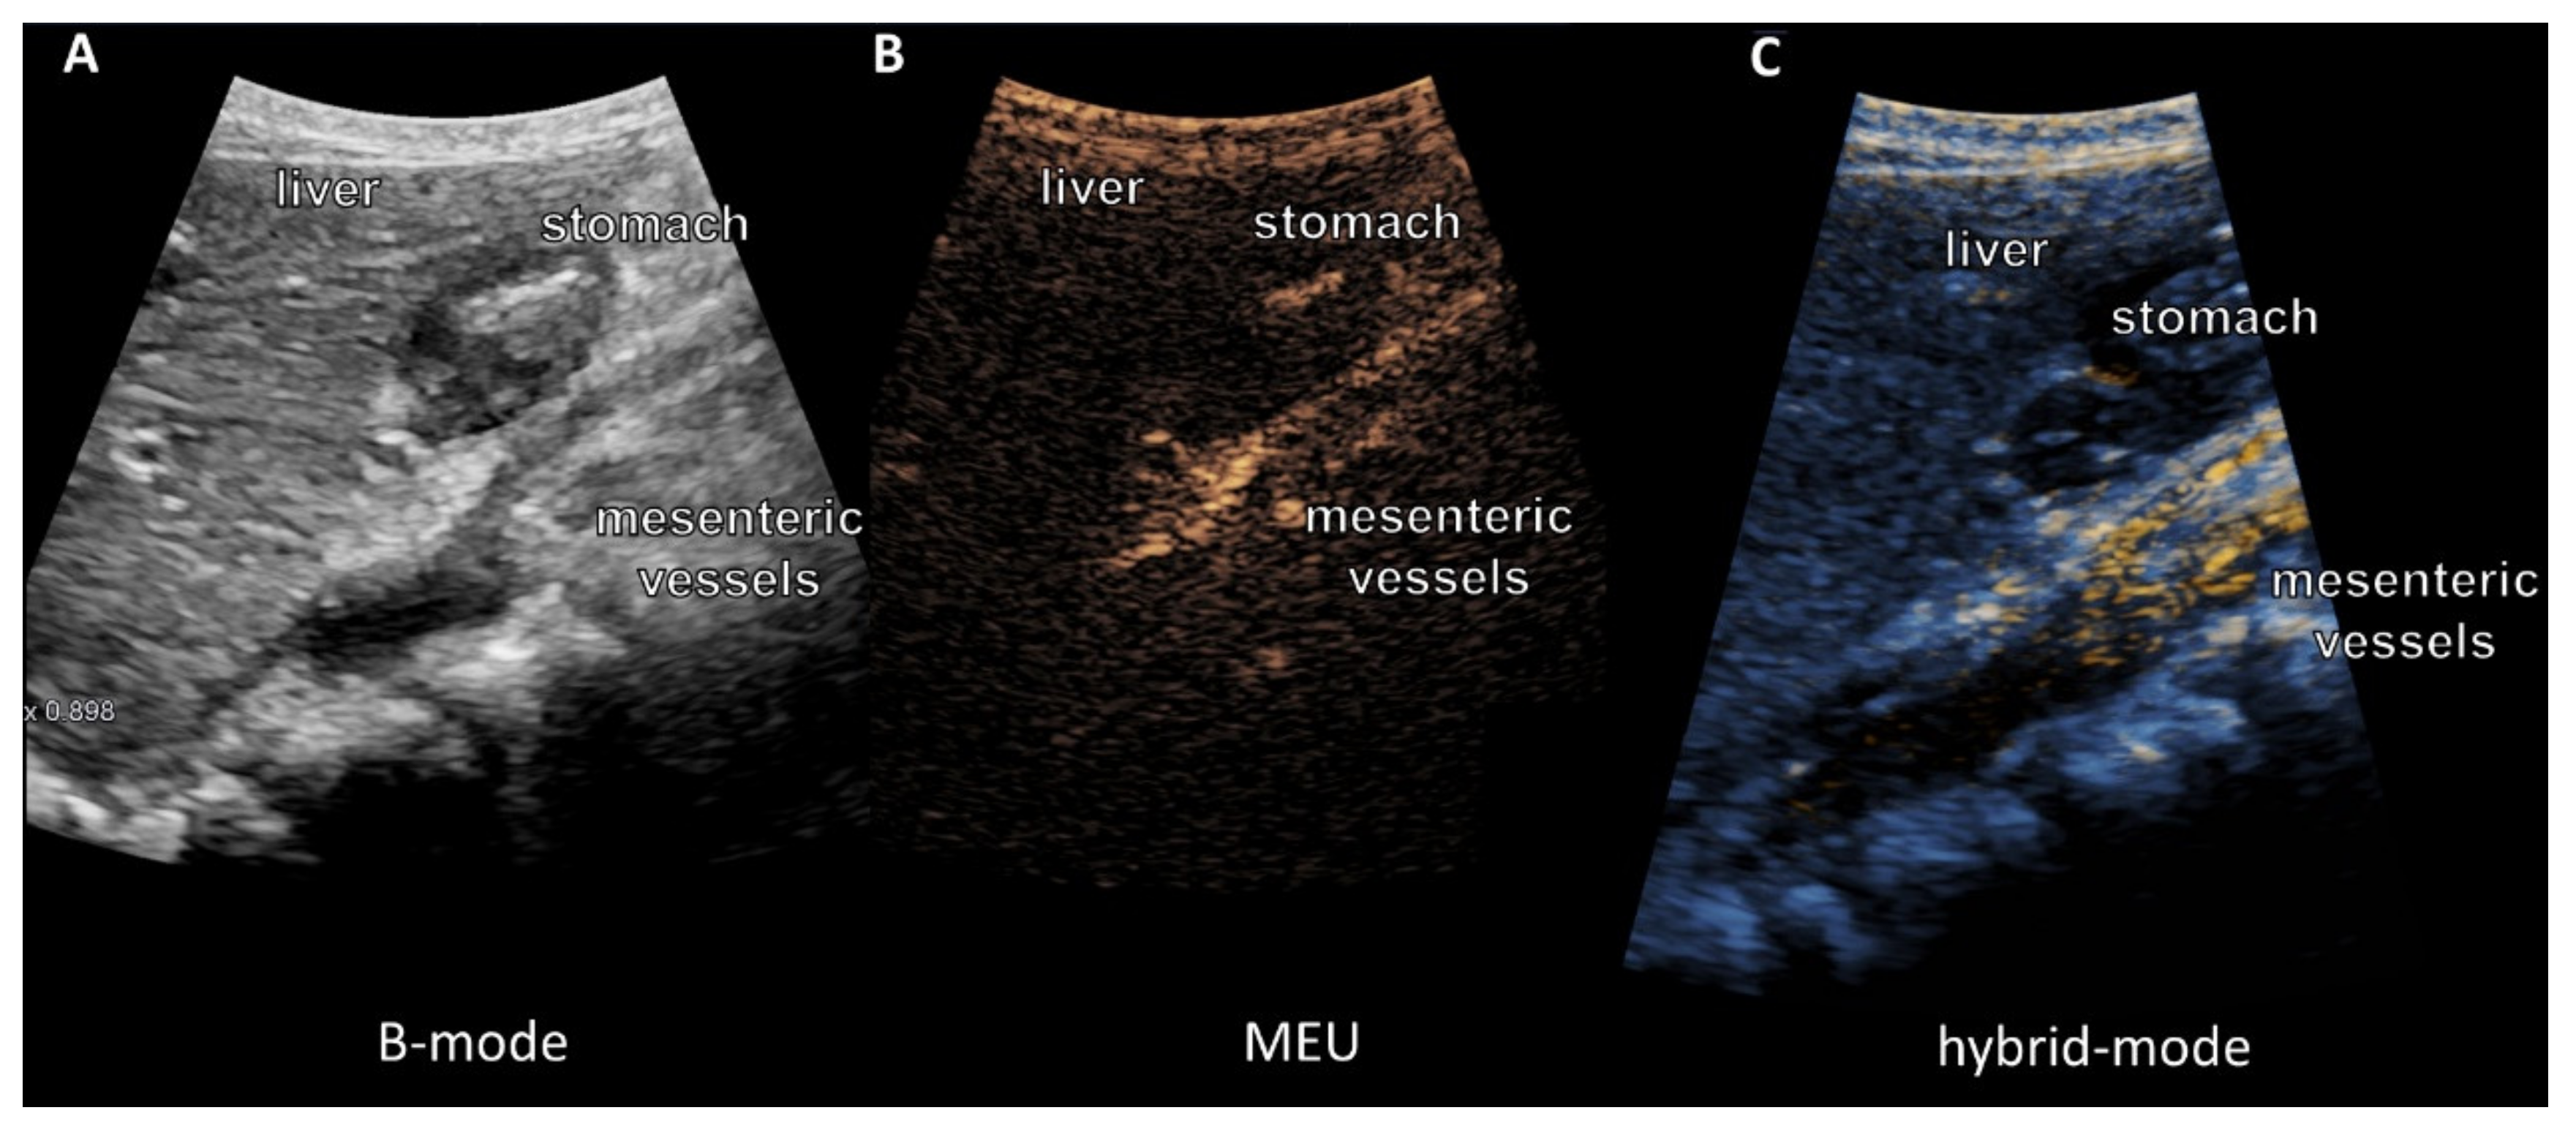

3.3. Ultrasound Examination of Intestinal Absorption